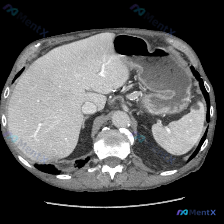

整理了一份有点「陷阱」的读片案例,先看一下基本情况: 影像基本信息 上腹部横断面CT(软组织窗),患者口服了对比剂(胃腔内高密度影为造影剂留影)。 读片所见(按器官逐一梳理) 1. 肝脏:实质密度均匀,未见明确占位,肝叶比例、形态大致正常; 2. 脾脏:划重点——形态规则,密度均匀,没有局灶性低密度...